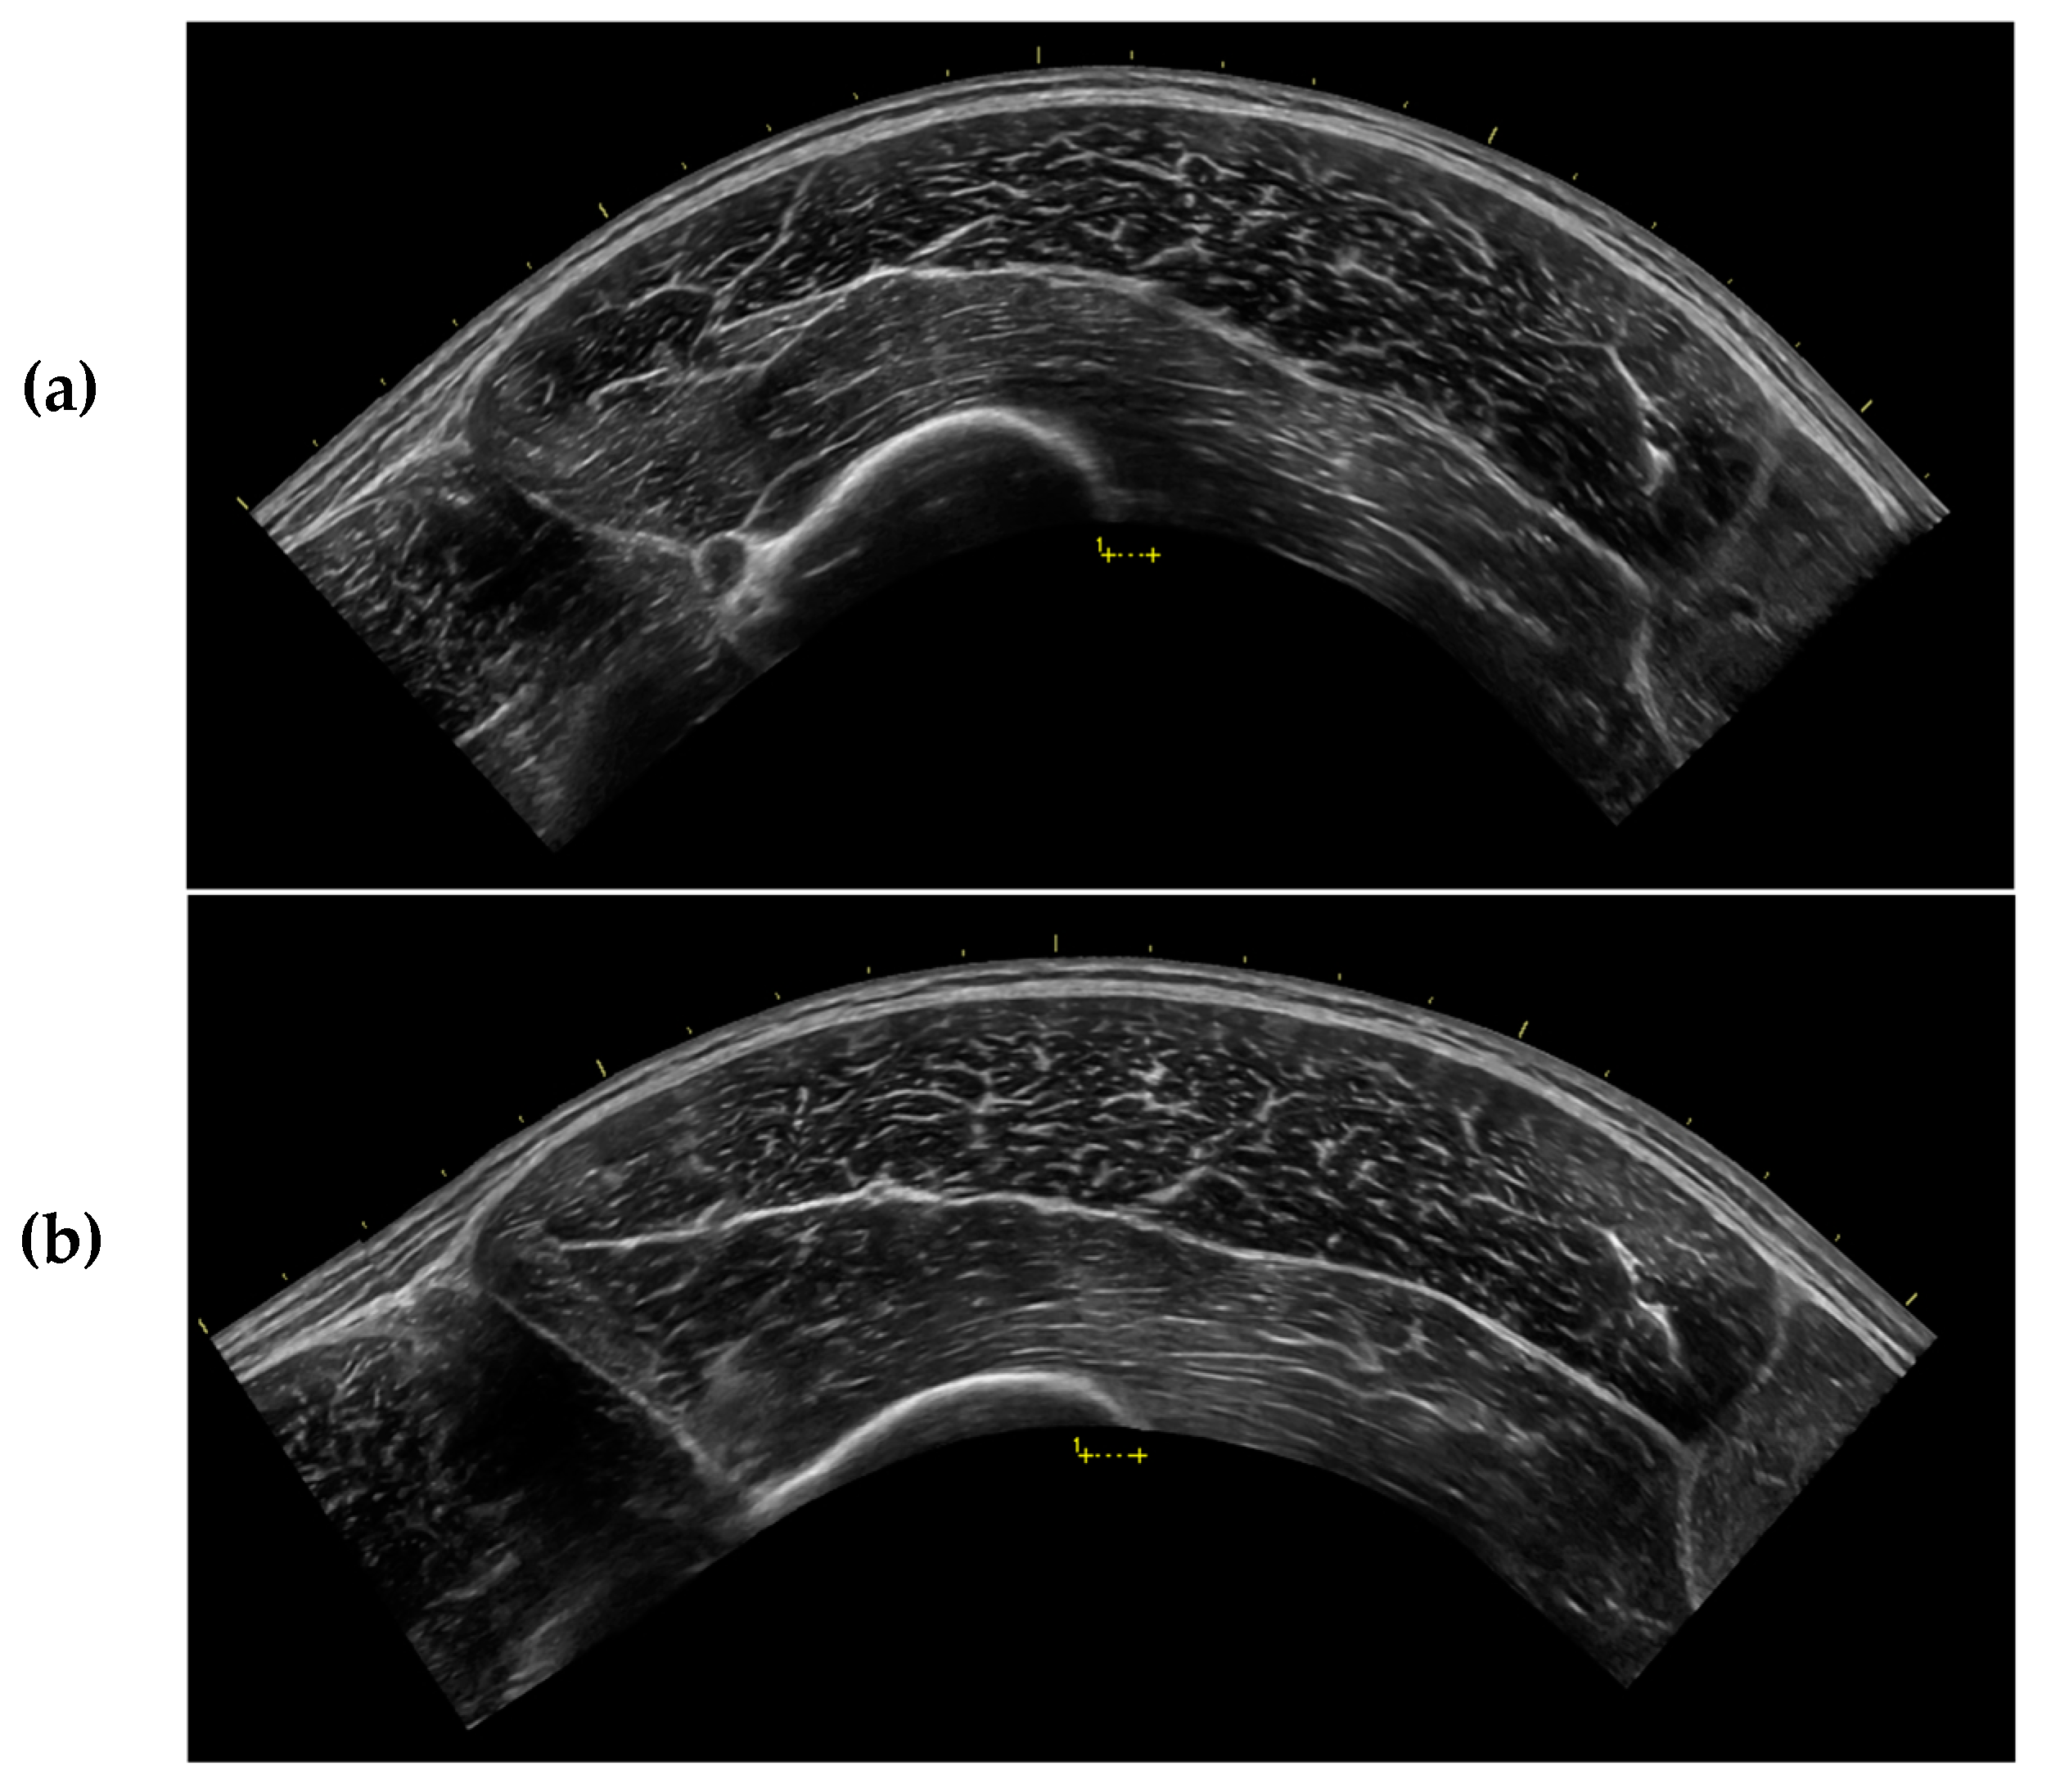

Each participant underwent five rounds of non-invasive ultrasound assessment of the VL in the dominant leg. Ultrasound rest positions are depicted in Figure 2a–d. For all lateral recumbent assessments, the participant’s legs were positioned to allow a 10° bend in the knees, as measured by a goniometer. Participant’s legs were stacked together, and a foam pad was placed between their ankles. For the first assessment, participants were positioned in the non-dominant lateral recumbent position (NDLR) (Figure 2a). Ultrasound images of the VL were captured immediately after the participant was positioned (IP). The assessments completed during IP took, on average, 113.9 ± 12.6 s to complete. Following IP, participants were instructed to remain in the NDLR position for 15 min, after which, additional ultrasound images were captured in the NDLR position. Following this, each participant was asked to stand for 15 min, and then asked to lay supine (SUP) on an examination table for 15 min (Figure 2b). Participants were then placed back in the NDLR position, and ultrasound assessments were taken immediately after the transition. Participants were again asked to stand for 15 min, and then asked to lay on an examination table in the dominant lateral recumbent (DLR) position for 15 min (Figure 2c). Participants were then placed back in the NDLR position, and ultrasound assessments were taken immediately after the transition. Participants were again asked to stand for 15 min, before being asked to stand on an elevated platform to obtain standing (ST) ultrasound images. While in the ST position, participants were instructed to bear weight only on their non-dominant limb, while the shin of the dominant limb rested against a higher platform to allow for a 10° bend in the knee (Figure 2d). Participants were instructed to completely relax the dominant leg against the higher limb to avoid muscle contraction of the VL. Ultrasound images were captured while participants remained in the standing position (ST), and were identical to those used during the recumbent positions. The order of all assessments except ST were randomized for each participant.

The current investigation demonstrated that MT of the VL was significantly greater in ST compared to all recumbent positions, and CSA was significantly greater in ST compared to all recumbent positions except IP, although a trend was observed between IP and ST. These findings align with those of Wagle et al. [15], indicating that measurements of muscle size taken at the muscle belly may be influenced by changes in position in the absence of changes in CSA. This may be a result of muscle “gearing” where muscle fibers shorten in the longitudinal direction and expand in the transverse direction. This causes the muscle fibers to rotate to a greater PA, which creates a bulging effect in the center of the muscle [46,47]. Consistent with this, we observed a significantly greater PA in ST compared to all other positions. Nevertheless, muscle gearing is typically reported during muscle contraction, when a change in the length of the muscle is induced [46]. In the present study, careful consideration was taken to ensure that joint angle remained constant and the muscle was relaxed in all positions examined. It is apparent that changes in position can create a similar muscle-bulging effect due to the influence of gravity on muscle shape and size [14,25] that may not be due to true muscle gearing. Anecdotally, we noted that the VL appeared flatter and longer in the recumbent positions compared to ST, which may have allowed for only modest changes in CSA as compared to the larger changes in MT [25] (Figure 3).